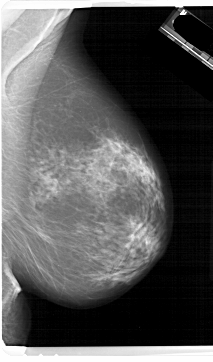

A_1657_1.LEFT_CC

LEFT_CC LINES 6691 PIXELS_PER_LINE 3856 BITS_PER_PIXEL 12 RESOLUTION 43.5 OVERLAY